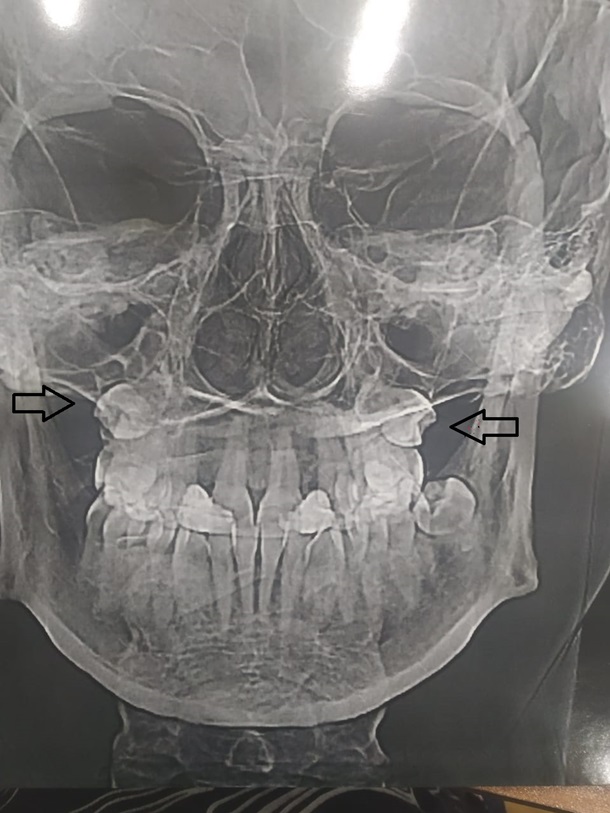

При прохождении МРТ, диагностика показала, что "четверки" у девушки все-таки выросли, только не во рту, а в носу.

Зубы в носу